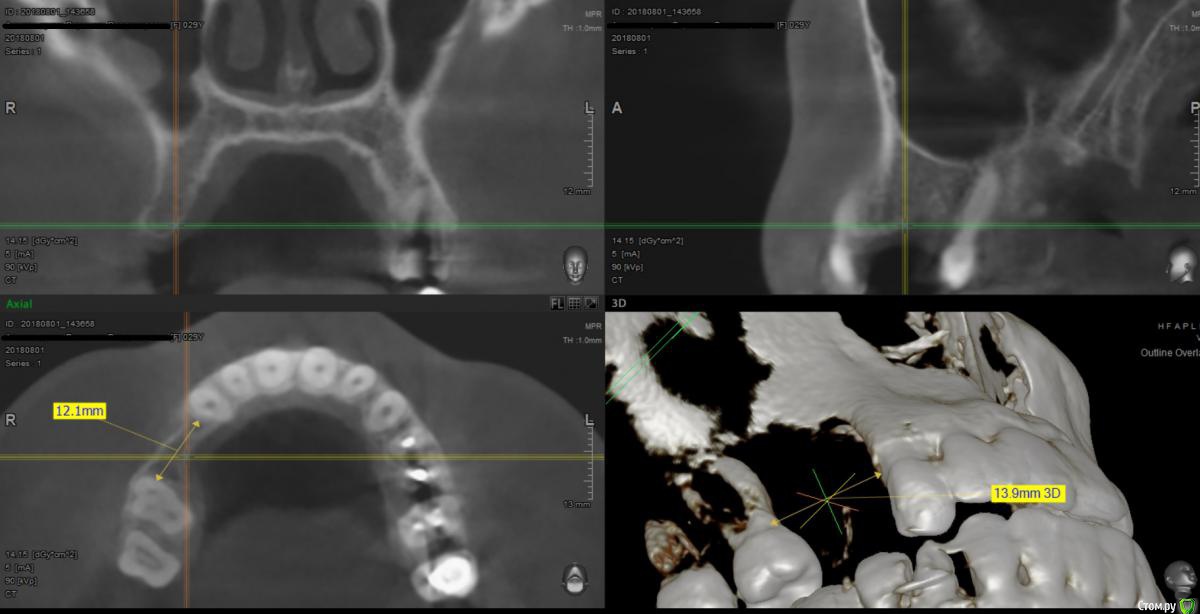

Foxtrot Опубликовано 29 августа, 2018 Поделиться Опубликовано 29 августа, 2018 Доброго времени суток! Как думаете стоит ли устанавливать 2 импланта, удастся ли добиться эстетики мягких тканей? Как бы вы поступили в данной ситуации? У меня пока 3 варианта:1) нкр + импланты - первым этапом, десна - вторым.2) нкр + сст - первым, времянки и еще десна (по ситуации) - вторым.3) 1 имплант, сст, времянка с консолью.Все в один этап как-то страшновато. Ссылка на комментарий

x4ex Опубликовано 29 августа, 2018 Поделиться Опубликовано 29 августа, 2018 (изменено) По всей видимости между экваторами 13 и 16 там около 10мм. Исходя из этого, я бы пошёл по 3 варианту с одним имплантатом нормальной ширины в области 15, только без немедленной нагрузки. Изменено 29 августа, 2018 пользователем x4ex Ссылка на комментарий

Тимур86 Опубликовано 29 августа, 2018 Поделиться Опубликовано 29 августа, 2018 ощущение что Вы чуть недомерили кость Ссылка на комментарий

Foxtrot Опубликовано 29 августа, 2018 Автор Поделиться Опубликовано 29 августа, 2018 ощущение что Вы чуть недомерили кость прошу прощения. Без очков не вижу Ссылка на комментарий